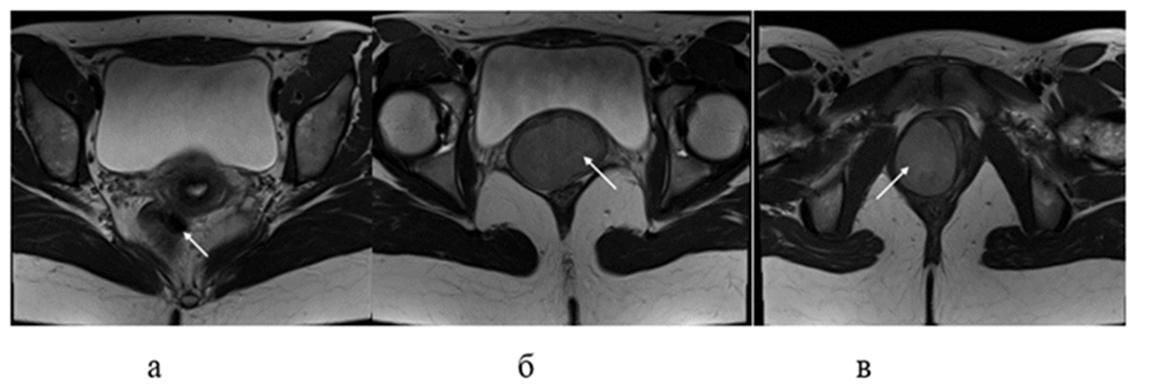

Contrast-enhanced MRI of the pelvis: The uterus is anteflexed, not enlarged: 50x45x53 mm. The cavity is not enlarged, the endometrium is homogeneous. The right ovary measures 32x24x26 mm and contains a moderate number of follicles. The left ovary measures 53x42x38 mm and is enlarged due to two cystic formations measuring 32.5x25x23 mm and 13.5x12.5x11 mm. In the vaginal lumen, on the anterior and right walls, two solid formations with a fairly homogeneous internal structure are determined, with a clear capsule, smooth contours, measuring 51x59x40.5 mm and 42x37x55.5 mm, with pronounced diffusion restriction. The latter formation is closely adjacent to the cervix without signs of infiltration. After the introduction of a contrast agent, its uneven accumulation in the formations is determined. Conclusion: MR image of two large solid formations in the pelvic-perineal region. MR data of focal formations of the left ovary of the endometrioid cyst type (Figs. 1 and 2).

Figure 2: MRI images of axial sections of the small pelvis: a – level of the cervix; b – level of the first formation; c – level of the second formation.